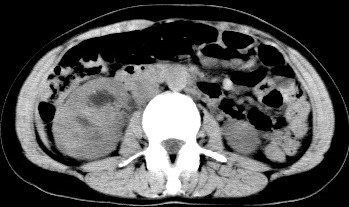

病历摘要:女性,35岁。右腰隐痛,排无痛性肉眼血尿9个月,体查右肾区轻度叩痛。行IVP及CT检查。